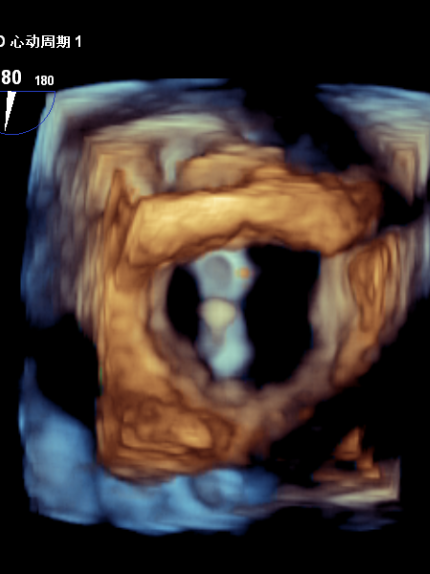

3D MV View: 二尖瓣前后瓣叶对合不全,A2/P2稍偏1区可见未闭间隙。PISIA主要来源于A2/P2区域。